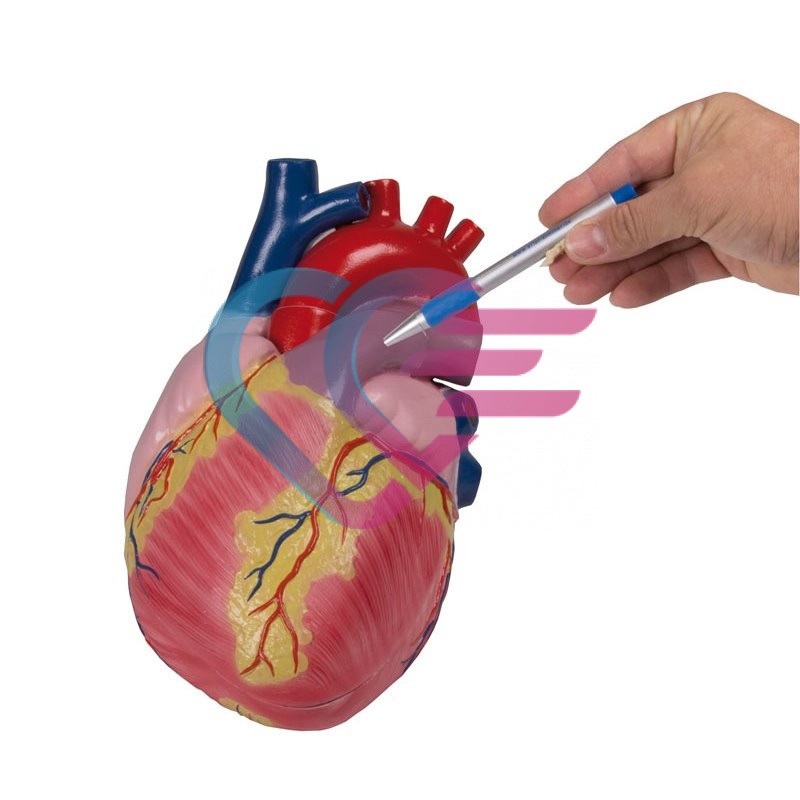

Povezani proizvodi